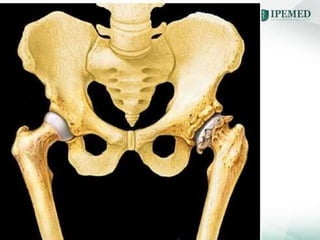

OSTEOARTROSE - QUADRIL

Oa ipemed parte i junho 2019